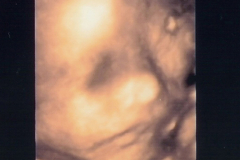

우리집 듬직(?)이 성호의 앨범입니다. 초상권 보호를 위해 어릴적 사진만 공개합니다.~